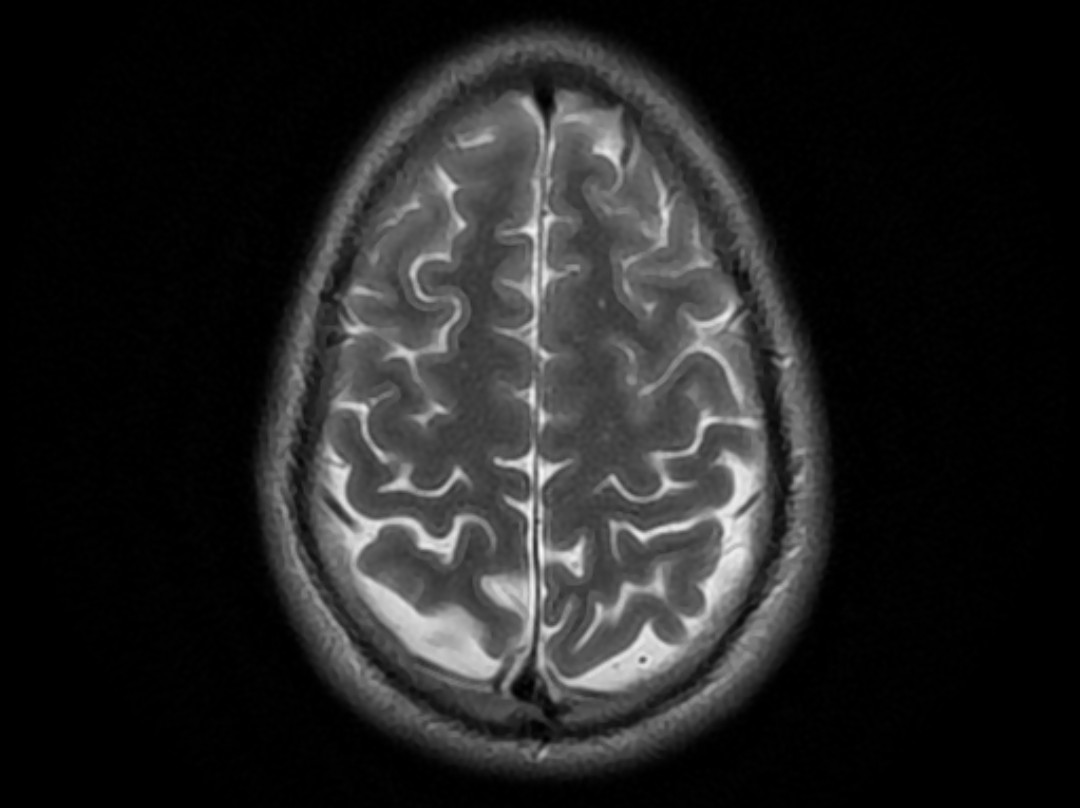

La difficulté, pour ce type de malformations, réside dans le fait qu’il y a « à l’intérieur du crâne du fœtus, un court-circuit entre les artères et les veines, qui se retrouvent branchées alors qu’elles ne devraient plus l’être », précise le Pr. Naggara. En temps normal, un fin réseau de vaisseaux sanguins, les capillaires, assurent la distribution de l’oxygène dans le cerveau. Ils sont le lien entre les artères, qui amènent sous pression le sang du coeur au cerveau, et les veines, par lesquelles le sang retourne vers le coeur. La malformation anévrismale de la veine de Galien touche le réseau capillaire se jetant dans la veine de Galien. Ces vaisseaux, malformés et dilatés, entraînent un court-circuit entre les artères et les veines situées dans la partie centrale du cerveau. Le sang artériel et le sang veineux convergent alors, privant le cerveau de l’oxygène dont il a besoin et perturbant également le cœur, précise le Pr Yves Ville, chef du Service d’Obstétrique et de Médecine Fœtale à l’Hôpital Necker. « Sur le plan embryologique », ajoute-il, « certains vaisseaux utiles à l’embryon, finissent par se reboucher car ils perdent leur utilité ». La persistance de certains vaisseaux peut être la cause de malformations.

La veine visée se trouve entre les deux hémisphères du cerveau. Le Pr. Naggara explique qu’il a dans un premier temps fallu procéder à des « manœuvres externes » sur le ventre de la mère, afin que l’enfant ait la bonne position pour l’opération, et présente ainsi « sa nuque dans la partie la plus convexe de l’abdomen de la maman ». C’est là le caractère essentiel d’une collaboration pluridisciplinaire dans les équipes chirurgicales, car une partie de l’opération reposait sur l’expertise obstétricale. Tout au long de l’intervention durant laquelle mère et enfant sont anesthésiés, un suivi continu est fait par échographie pour guider le geste chirurgical.